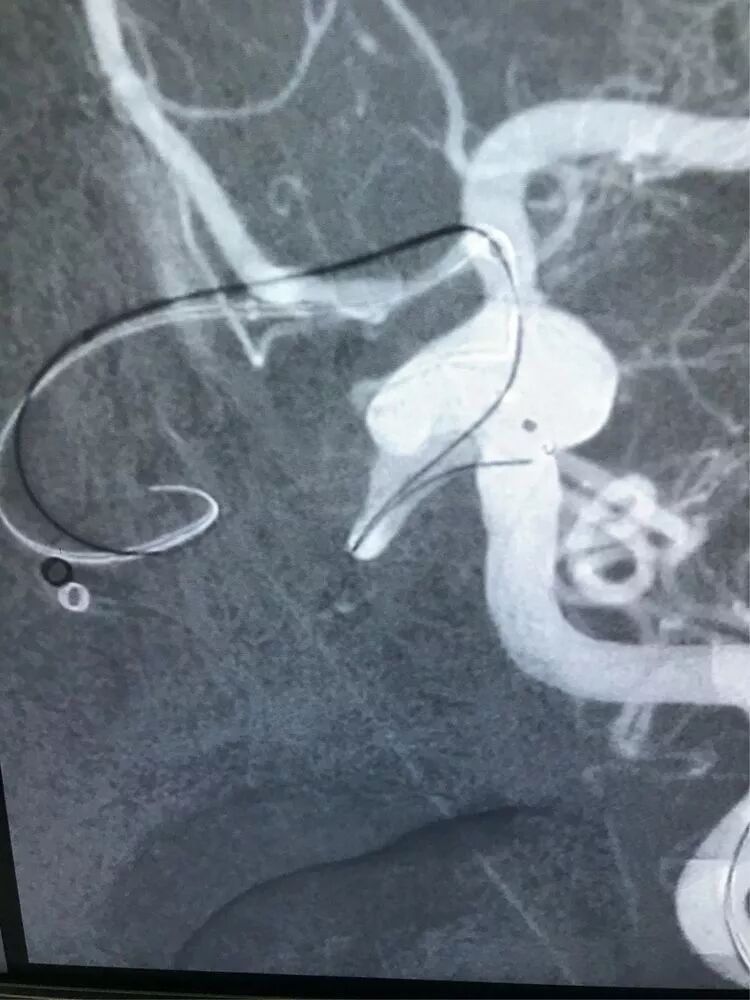

Enterprise4.5×22支架半释放,支架尾端的有效段能恰好覆盖全瘤颈

支架有效段完全释放,这个时候开始将支架导管往前顶,让导管头端尽量越过瘤颈远端

支架完全释放

释放后的造影。突入颈内动脉和后交通动脉内的弹簧圈被压入瘤体内

继续填塞,后面就简单了。最后的结果,一共用了四枚弹簧圈,栓塞致密,瘤体及破口都不显影了